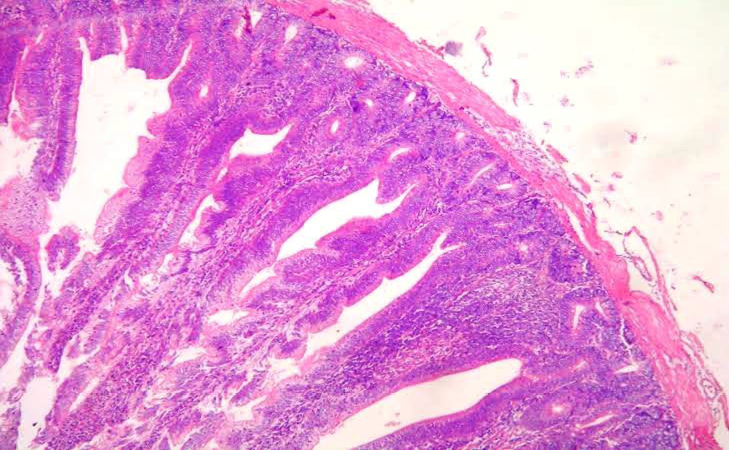

Figure 2

Section of intestine showing sloughing of villli and heterophillic infiltration)